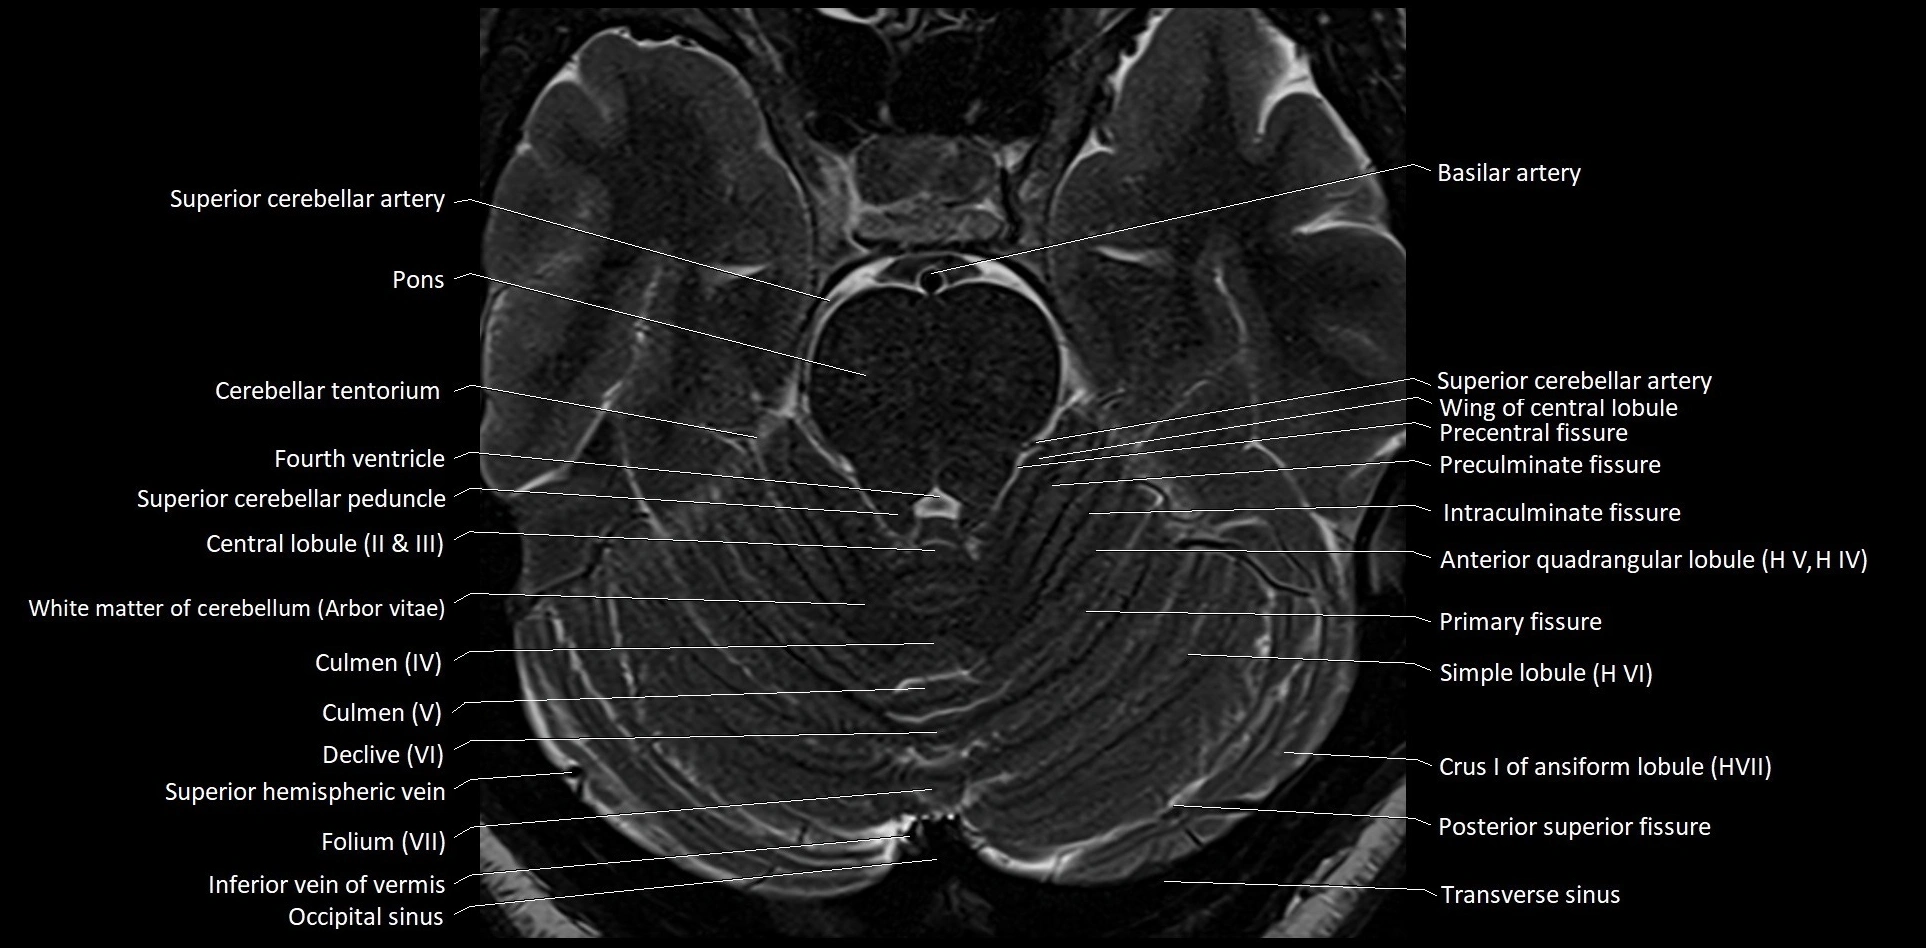

- Central lobule (II & III) of Cerebellum

- Cerebellar tentorium

- Culmen

- Culmen (IV, V) of Cerebellum

- Declive

- Declive (VI) of Cerebellum

- Folium (VII) of Cerebellum

- Inferior vein of vermis

- Occipital sinus

- Posterior superior fissure

- Precentral fissure

- Preculminate fissure

- Primary fissure

- Simple lobule

- Simple lobule (HVI) of cerebellum

- Superior cerebellar peduncle

- Transverse sinus

- Wing of central lobule